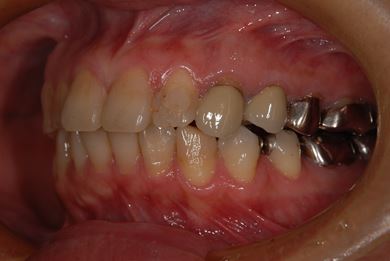

インプラントの症例写真 IMPLANT

骨再生インプラント治療

| 性別/年齢 | 女性 / 46歳 | ||||||||||||||||||||||||||||||||

| 主訴 | 歯ぐきがただれてる。歯が少しうずく。 | ||||||||||||||||||||||||||||||||

| 治療方針 | インプラント治療にて、機能的・審美的回復を行う。 | ||||||||||||||||||||||||||||||||

| 治療内容 | インプラント1本(GBR)、ハイブリッドセラミック1本 | ||||||||||||||||||||||||||||||||

| 総治療費 | 368,655円 | ||||||||||||||||||||||||||||||||

| 治療期間 | 7ヶ月 |